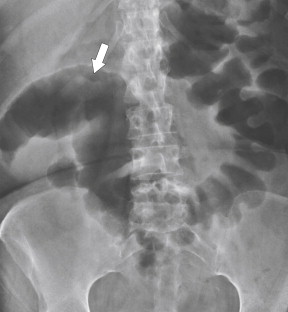

Plain radiography may demonstrate an ileus, sometimes confined to the left colon. As the disease progresses, bowel wall thickening develops ( Fig. 5-34 ) with a toxic megacolon if severe ( Fig. 5-35 ). BE is now rarely performed, but results demonstrate thickened folds and ulceration, either linear or with mucosal sloughing. Healing can lead to stricture formation ( Fig. 5-36 ). The findings are now usually made by CT and are similar to other forms of colitis (inflammatory bowel disease, infectious colitides, and radiation colitis if the radiation field included the colon). The disease is suggested in the appropriate clinical setting and by the left-sided distribution of the colonic changes ( Fig. 5-37 ). Severely affected patients show colonic pneumatosis as the gas permeates the damaged mucosa, which can then enter the mesenteric venous system and be recognized as mesenteric venous gas (particularly at CT) and ultimately intrahepatic portal venous gas. Occasionally, ischemia occurs proximal to an obstructing colonic stricture, such as colonic adenocarcinoma. The obstruction causes marked distention of the proximal colon, compromising its vascular supply or directly invading mesenteric vasculature ( Fig. 5-38 ).

Figure 5-34, Plain abdominal radiograph in a 78-year-old woman with left-sided colonic wall thickening ( arrows ) due to ischemic colitis.

Figure 5-35, A and B, Plain abdominal radiograph ( A ) and magnified view ( B ) in a 56-year-old man with a left-sided toxic megacolon due to ischemic colitis. There is thumb-printing of the colonic mucosa at the splenic flexure ( arrows ).